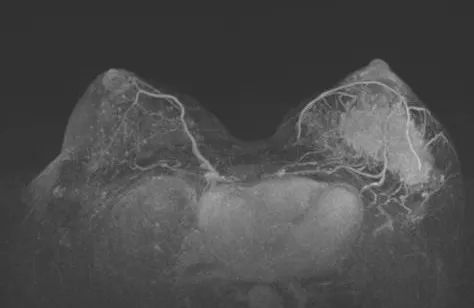

2021-11 乳腺MRI:左乳上份、外上象限见一不规则等T1,等-稍长T2信号肿块,大小约8.2cm×3.7cm×6.5cm,ADC值最低处0.71×10E-3mm2/s,动态增强扫描不均匀显著强化。左腋下多枚肿大淋巴结,大者约2.2cm×1.3cm,增强明显不均匀强化。形状呈不规则,边界欠清楚。

图2. 新辅助治疗前乳腺MRI

图3. 上图为治疗前,下图为治疗6周期后

治疗6个周期后,乳腺增强MRI显示靶病灶明显缩小,临床疗效评估为PR;腋窝靶病灶消失,临床疗效评估为CR。